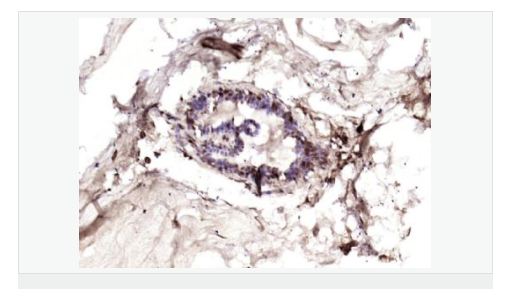

交叉反應:Human(predicted:Mouse,Rat) 推薦應用:IHC-P,IHC-F,IF,ELISA

產品應用ELISA=1:5000-10000 IHC-P=1:100-500 IHC-F=1:100-500 IF=1:100-500 (石蠟切片需做抗原修復)

細胞定位細胞核 細胞漿 細胞膜